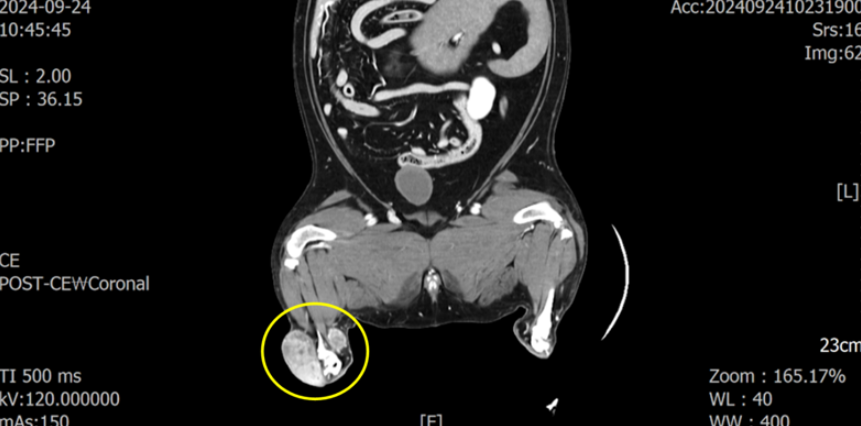

CT 촬영을 통해 해당 종양이 아킬레스건 주변을 둘러싸고 근육 침습도 일으키고 있는 양상을 확인하였습니다.

.png)

원격 전이를 의심할 만한 소견은 없었지만 인접한 림프절 중 하나인 sublumbar LN(요추하 림프절이 커져 있었습니다.